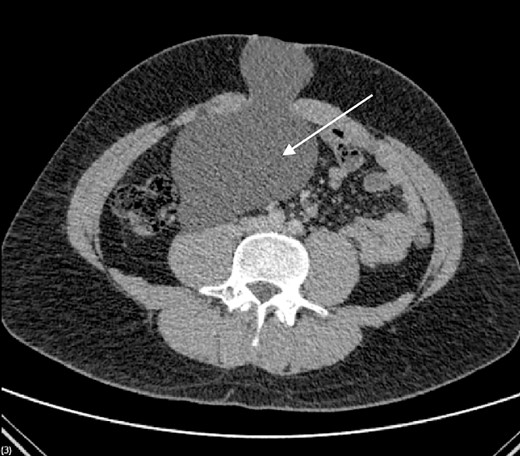

We present the case of a 26-year-old man who presented to the general surgery outpatient clinic with intermittent peri-umbilical pain, and the presence of a soft swelling palpable at his umbilicus. There was a positive cough impulse consistent with a true umbilical hernia and the patient described no previous medical or surgical history. An abdominal ultrasound scan visualized a large thin-walled serous fluid collection tracking into the peritoneal cavity (95 mm × 87 mm × 97 mm) (Fig. 1). Computed tomography (CT) of the abdomen and pelvis with contrast reported a large bi-lobed cystic mass centred at the right side of the mesentery, with herniation of part of the cyst along the umbilicus. Displacement of the small bowel with anterior extension into the abdominal wall was seen with the suggestion of posterior extension into the right retroperitoneal space (Figs 2 and 3). The patient underwent routine pre-operative work up and the cyst was excised through a midline para-umbilical laparotomy (Fig. 4) given the concern of retroperitoneal involvement. Intra-operatively, the hernia neck and the root of the cyst were found at the base of the umbilical cicatrix with no attachment to the mesentery. The cyst was loculated and filled with clear fluid. It was dissected off the peritoneal tissues and off from the posterior umbilical skin prior to removal. There was evidence of rupture of one of the locules and clear fluid was drained.